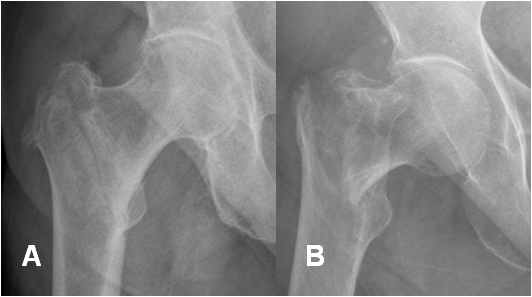

Fig 53. Fractura intertrocantérica.

A y B: Rx AP. En A fractura lineal y en B fractura desplazada.